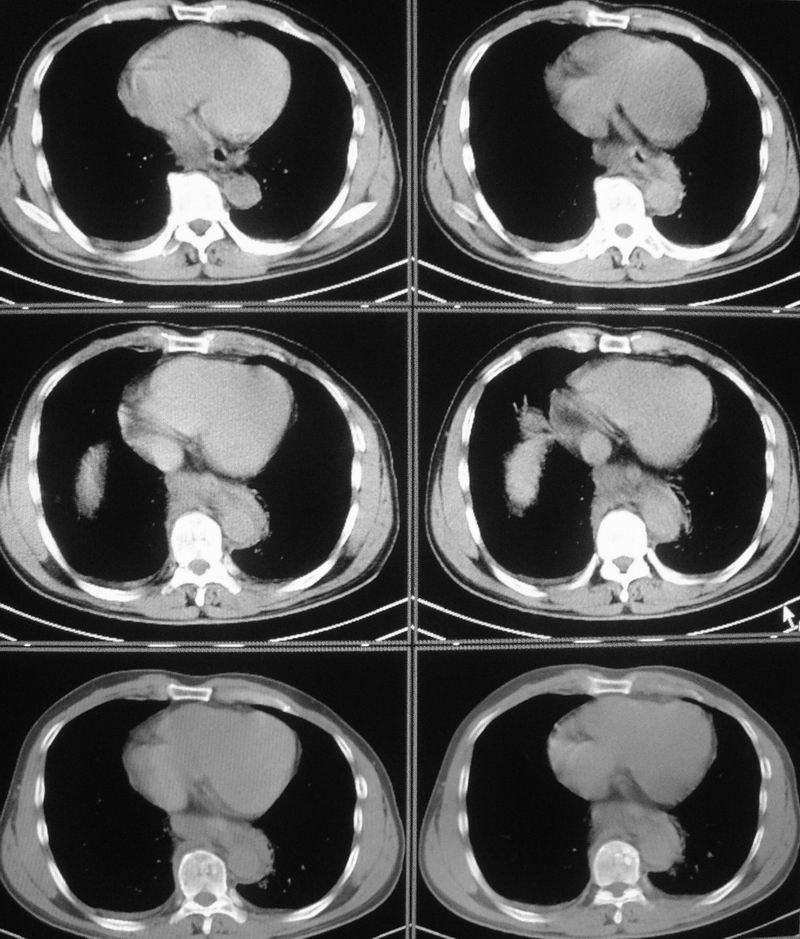

男性,47岁,车祸致胸痛2小时。

请大家看看后纵隔食道及降主动脉周围的软组织密度灶是什么?双侧膈肌脚内侧及椎管内的气体影是怎么回事?

考虑纵隔外伤后积血。

右肺下叶血肿形成。

结合病史多考虑纵隔血肿形成

有外伤病史,两个征象应该认为是外伤所致出血;需再确认是否有骨折,导致的积气。

是后纵隔出血还是出血合并有胸主动脉加层,增强扫描.

结合病史多考虑纵隔血肿形成 ,椎管及右侧腰大肌内侧气体影也与外伤有关。

要不要考虑食道中下段的损伤呢?这样血肿和气体影就都好解释了。